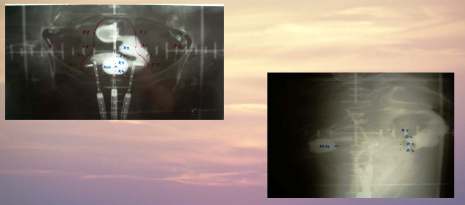

Ozařovací techniky

Negativní lymfografie:

- Box technika

Pozitivní lymfografie:

- Ozáření pánve a paraaortálních uzlin

- Ozáření parametrii

Box technika:

- Technika 4 polí, kdy paprsky protilehlých polí leží v rovině sagitální a frontální

Ozáření pánve a paraaortálních uzlin

- Ozáření ze čtyř polí

- AP a PA pole ozařováno z OK 120 cm

- SIN a DX pole ozařováno z OK 103 cm

- Pole jsou vykryta individuálními bloky, které jsou

zakreslena

do snímku dle postižení

Ozáření parametrií

- Ozáření technikou dvou protilehlých AP/PA polí s centrálním individuálním vykrytím, které je vyrobeno po první uterovaginální aplikaci